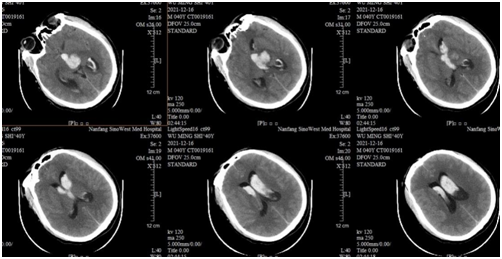

回忆起刚接诊的时候,急诊科李平主治医师介绍,患者多次呕出咖啡色的呕吐物,体格检查时发现血压高达193/119mmHg。急诊查颅脑CT提示左侧基底节区出血,蛛网膜下腔出血。

术前左侧基底节区出血破入脑室系统。通讯员供图

神经医学中心兼神经外科主任陈陆馗仔细检查,指出,患者左侧基底节区出血破入脑室系统,脑室扩张,随时有生命危险,必须争分夺秒进行“双侧脑室钻孔外引流术”,充分引流脑室内积血。

在麻醉科主任宁雪等医护人员的紧密配合下,神经外科张建锋主治医师成功为“无名氏”完成手术,术程顺利,术后复查头颅CT提示积血清除干净,患者生命体征逐渐稳定。

术后复查头颅CT提示积血清除干净